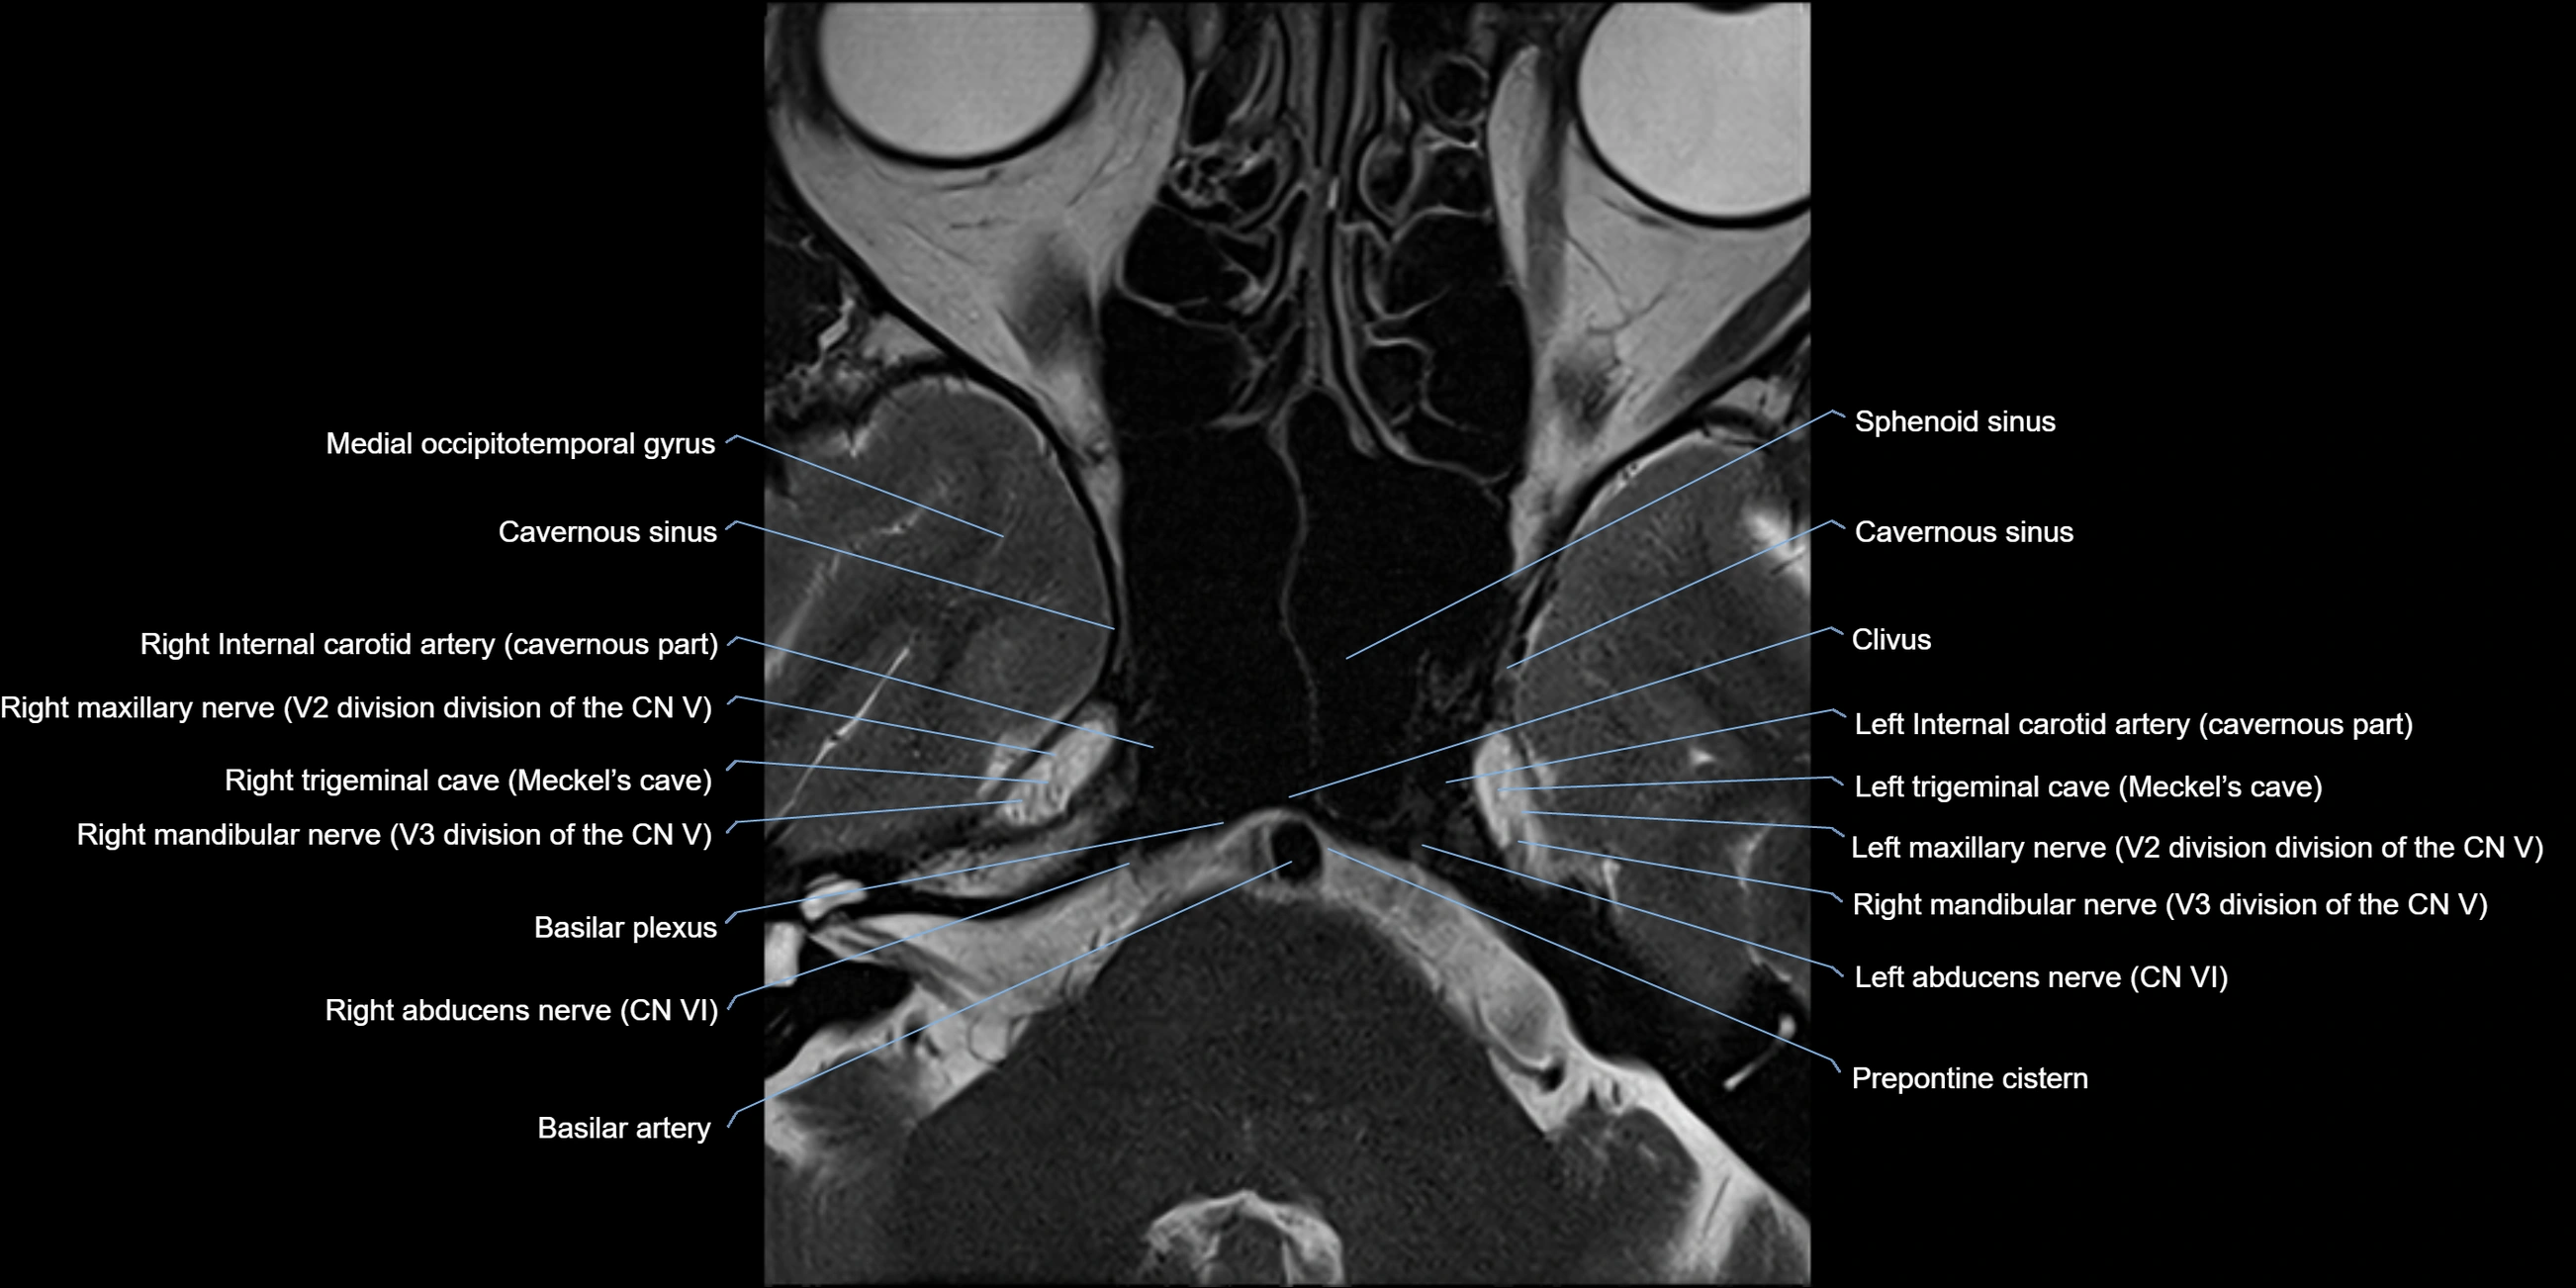

MRI Appearance

-

The abducens nerve is a small, thin, linear structure

Best visualized on high-resolution T2-weighted 3D MRI sequences (e.g., FIESTA or CISS)

Seen as a hypointense (dark) line running from the brainstem at the pontomedullary junction, traversing the prepontine cistern, and entering Dorello’s canal under the petrosphenoidal ligament, then into the cavernous sinus, and finally the orbit

May be challenging to visualize in standard MRI due to its small size

Pathology may be inferred by absence, displacement, or enhancement of the nerve

MRI images